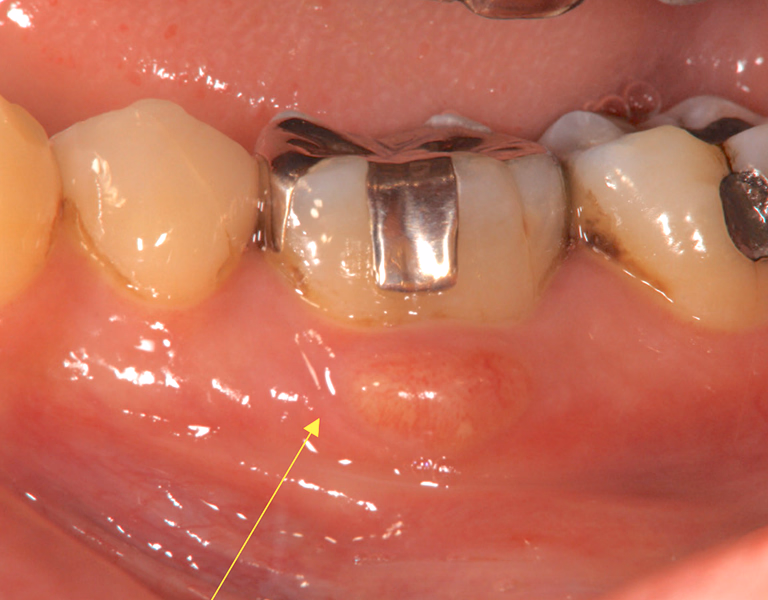

通常の根管治療では消失しなかった大きな根尖病変に対し外科的処置を追加。

1年後には病変の消失と症状の改善が確認できました。

今後も定期チェックで長期安定を図ります。